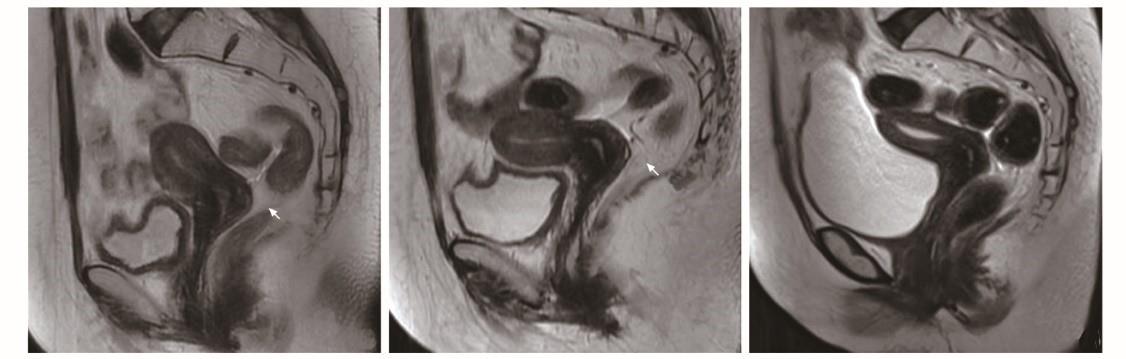

患者放疗前盆腔MRI图像示宫颈环周略长T2高信号 (箭头)

患者放疗后盆腔MRI图像A.放疗26次后宫颈环周略长T2高信号(箭头);B.放疗后1个月宫颈T2信号较前降低(箭头);C.放疗后4个月宫颈未见异常信号